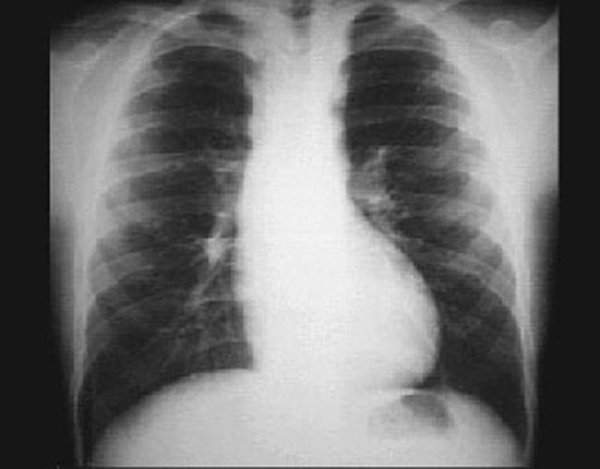

Rib notching is typically seen in patients with coarctation of the aorta, where collateral circulation in the intercostal arteries causes them to become large and tortuous and erode the adjacent inferior rib margins. This produces a scalloped or notched appearance and illustrates the importance of evaluating the chest X ray for bone abnormalities.

In this patient's chest X ray, rib notching is well seen in the posterior fourth to seventh ribs.